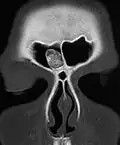

Osteome sind gutartige Knochentumore. Sie besitzen ein langsames Wachstum und bestehen aus einer lokalisierten Neubildung von Knochensubstanz. Am häufigsten entstehen sie im Bereich des Schädels, insbesondere in den Nasennebenhöhlen.

Da sie meist keine Symptome verursachen, werden sie oftmals nur zufällig ab einer gewissen Größenzunahme des Knochens entdeckt. Nachgewiesen werden sie oft im Röntgenbild, wo sie sich schattengebend und scharf begrenzt darstellen. Mit ihrer elfenbeinartigen Farbe heben sie sich oft vom restlichen Knochengewebe ab. Unter dem Mikroskop zeigt sich ausgereiftes und vollständig mineralisiertes Knochengewebe mit in Lamellen angeordneter Schichtung.